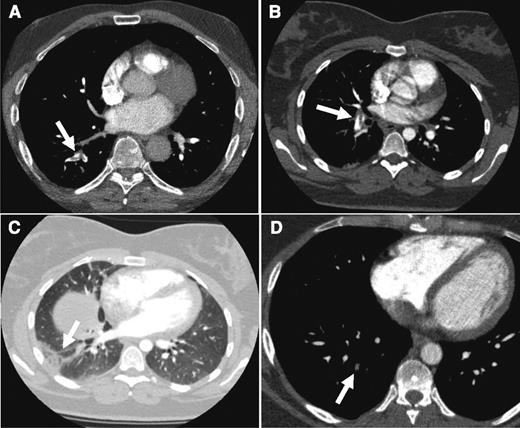

As for our patient, both the Wells rule and the revised Geneva score indicated an unlikely probability (Wells score: 3 points for PE as the most likely diagnosis; revised Geneva score: 1 point for age >65 years). Subsequent laboratory testing revealed an elevated d-dimer level of 2200 µg/L. Even when an age-dependent cutoff was applied (age 69, adjusted d-dimer cutoff 69 × 10 = 690 µg/L), this concentration was well above the normal threshold. Consequently, the patient was subjected to CTPA that confirmed a fresh embolus in the segmental artery to the right lower lobe (Figure 2A).

CTPA results from the cases. CTPA of patients from case 1 (A: arrow indicates acute thrombus in segmental artery to the right lower lobe), case 2 (B: despite breathing artifacts, clear visualization of acute PE in right segmental artery; C: arrow shows a wedge-shaped peripheral consolidation indicative of pulmonary infarction), and case 3 (D: arrow points to an organizing mural thrombus in a right basal segmental pulmonary artery).